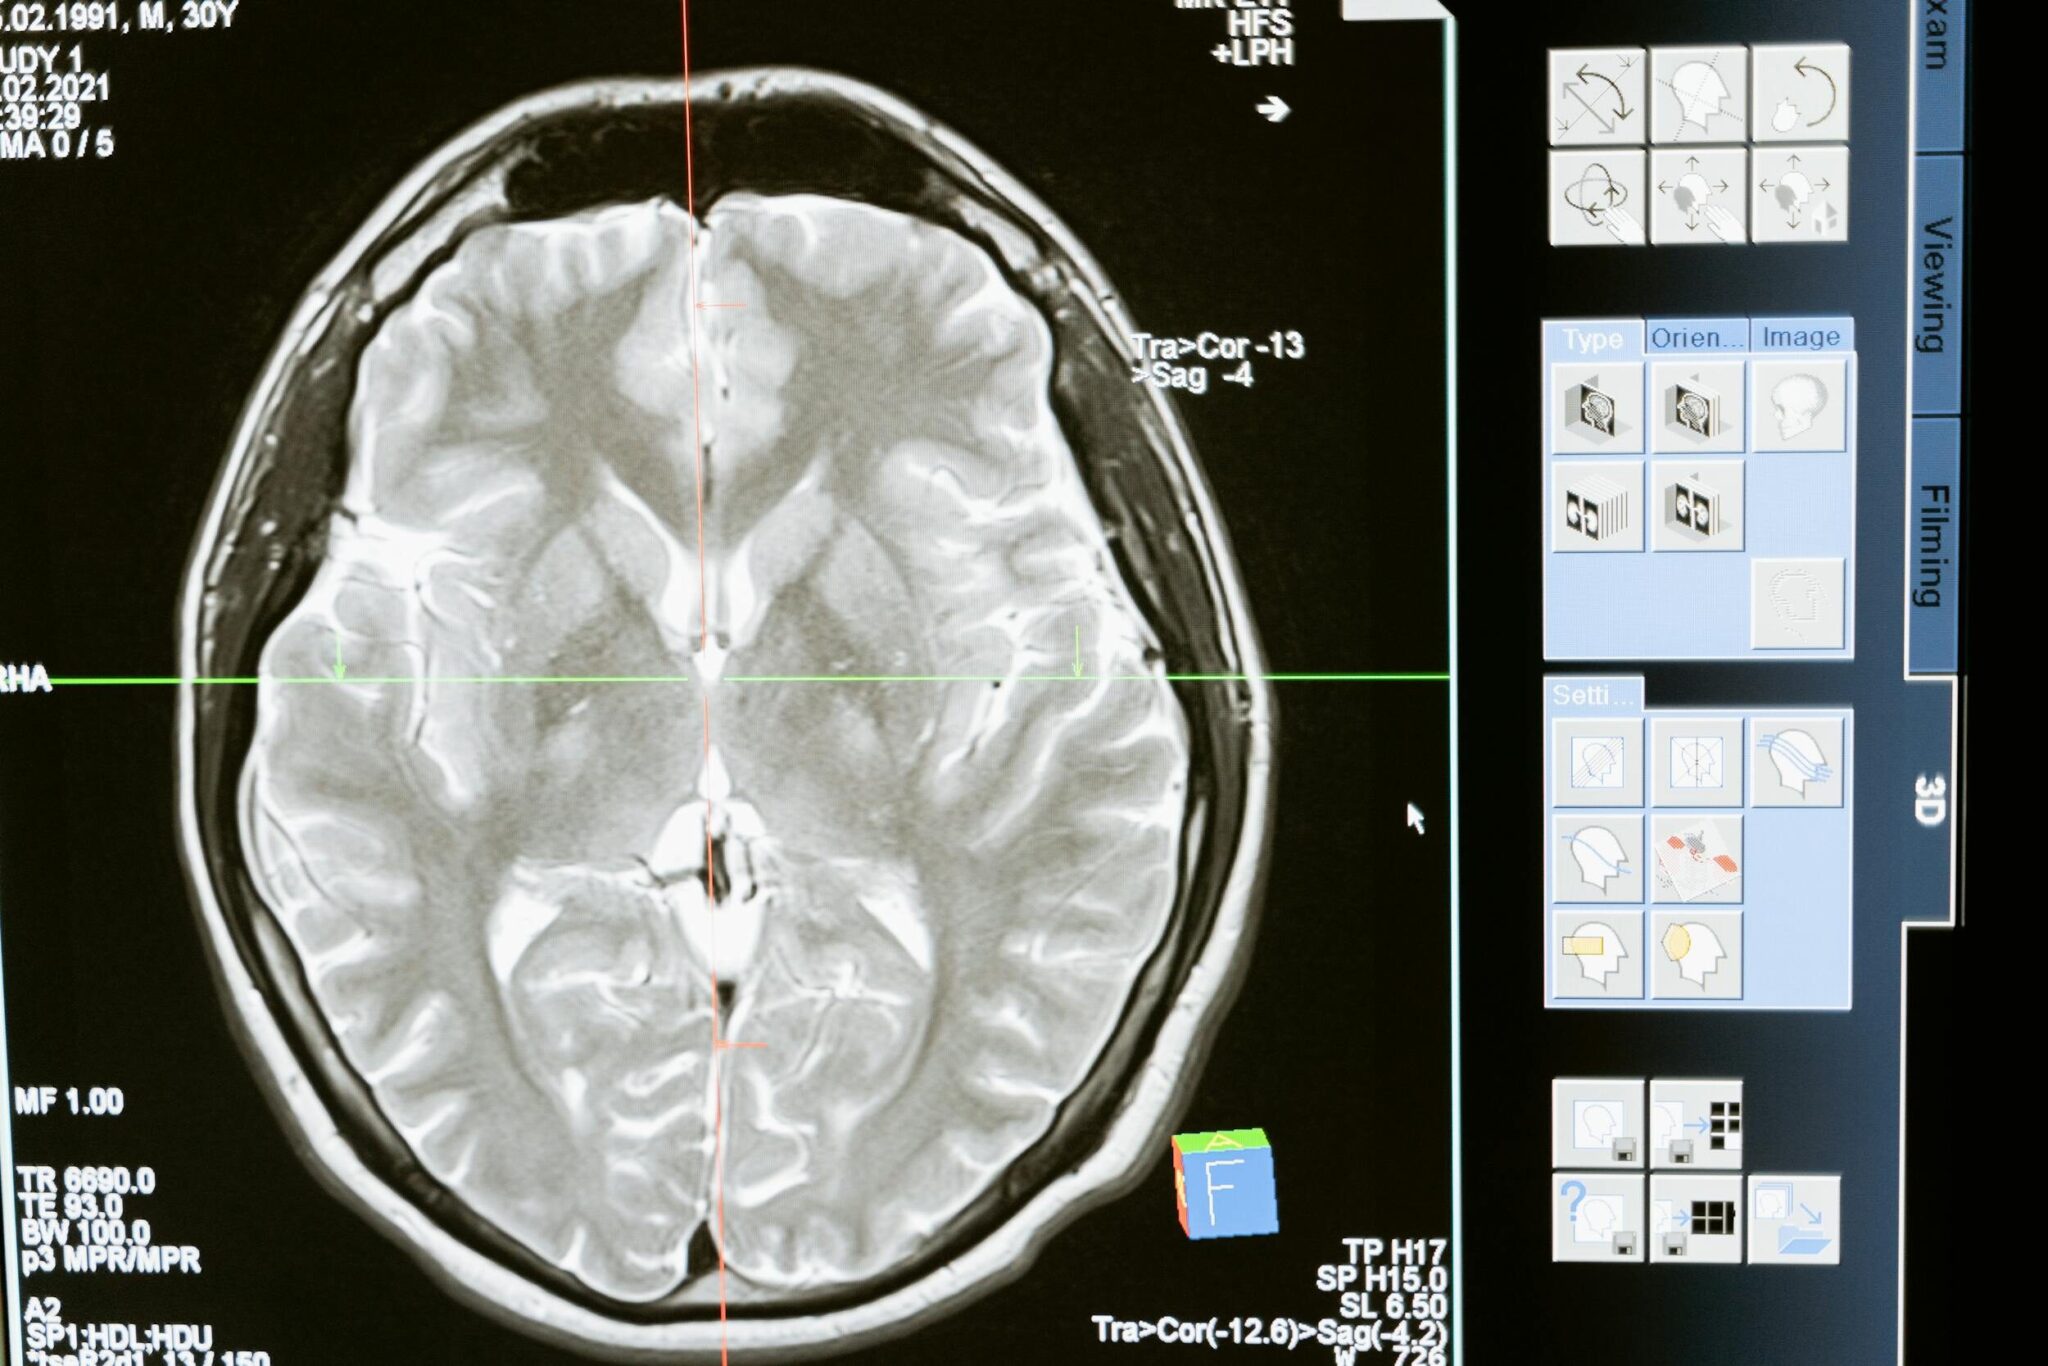

À l’arrivée aux urgences, le médecin de garde évalue avec précision le niveau de conscience et la force musculaire globale. L’investigation repose ensuite sur l’imagerie médicale afin de déterminer la nature de la lésion neurologique. Le scanner crânien identifie l’hémorragie avec une grande fiabilité. L’imagerie par résonance magnétique (IRM) excelle dans la détection précoce des zones ischémiées. L’angiographie met en évidence les occlusions artérielles. En parallèle, des analyses sanguines recherchent des troubles de la coagulation ou des infections sous-jacentes. L’électrocardiogramme et l’échocardiographie complètent le bilan pour évaluer le risque cardiaque.